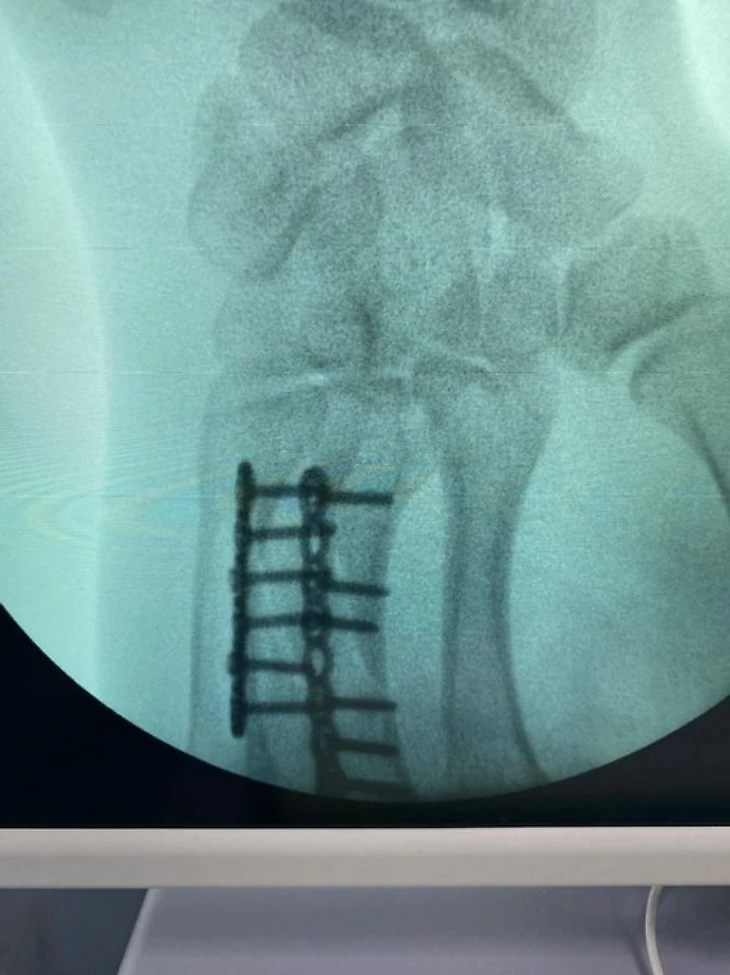

— Закрытый неосложнённый винтообразный перелом диафизов третьей и четвёртой пястных костей правой кисти со смещением отломков. Именно смещение и стало показанием для операции.

Если бы Непряева не была спортсменкой, мы проводили бы операцию иначе: скрепили бы отломки не пластинами, а винтами. При длинной плоскости перелома технология предполагает именно это. Но так как очевидно, что Наташа будет нагружать руку не как обычный человек, а в гораздо большей степени, для более прочной и надёжной фиксации было решено скреплять сломанные кости пластинами. Это, помимо всего прочего, позволяет человеку гораздо быстрее вернуться в строй.

Сергей Астахов твиттер : Так выглядит рука Натальи Непряевой после сложной операции. Сломанные пальцы собирали в течение часа.

Наталья Непряева @natali_nepryaeva прооперирована в АНО ЦКБ Святителя Алексия Митрополита Московского, руководителем центра микрохирургии кисти, реконструктивной и пластической хирургии, к.м.н., доцент кафедры травматологии и ортопедии РНИМУ им. Пирогова - Калантырской Валентиной Анатольевной.Была выполнена реконструкция пястных костей 3 и 4 пальцев правой кисти при помощи специальных пластин.Сроки восстановления около 3-4 недель.После осмотра врача 1 февраля Наталья планирует свое возвращение в команду.